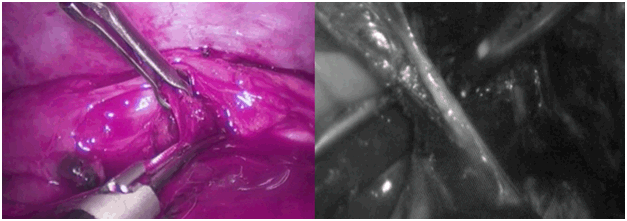

Patient 3: A 54-year-old female presented with complaints of severe progressive dysphagia, nausea and vomiting for last 3-4 months. Computed tomography (CT) scan and endoscopy with biopsy reveled T3N0 squamous cell carcinoma. The patient was planned for a Minimally Invasive Esophagectomy. The operation was carried out successfully with 25 lymph node resections and clear margins. The operative time was six and a half hours. The patient had an extended ICU stay of 21 days and a hospital stay of 30 days due to anastomotic leak and thoracic duct leakage which eventually resolved on NPO and total parenteral nutrition. The patient is doing fine at follow-up of seven months now. A still picture from videoscopic procedure showing division of left gastric pedicel (left) and esophageal mobilization (right) is shown in figure 4.

Figure 4: Videoscopic clip picture - division of left gastric pedicel (left), circumferential esophageal mobilization (right).